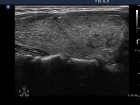

First examination (first row):

Clinical presentation: A 29-year-old woman was referred for evaluation of complaints suggesting hyperthyroidism. She had no eye signs.

Palpation: Both lobes were enlarged. No nodule was palpable.

Ultrasonography: Both lobes were enlarged, moderately hypoechogenic, inhomogeneous and displayed increased vascularization.

Diagnosis: Graves' hyperthyroidism.